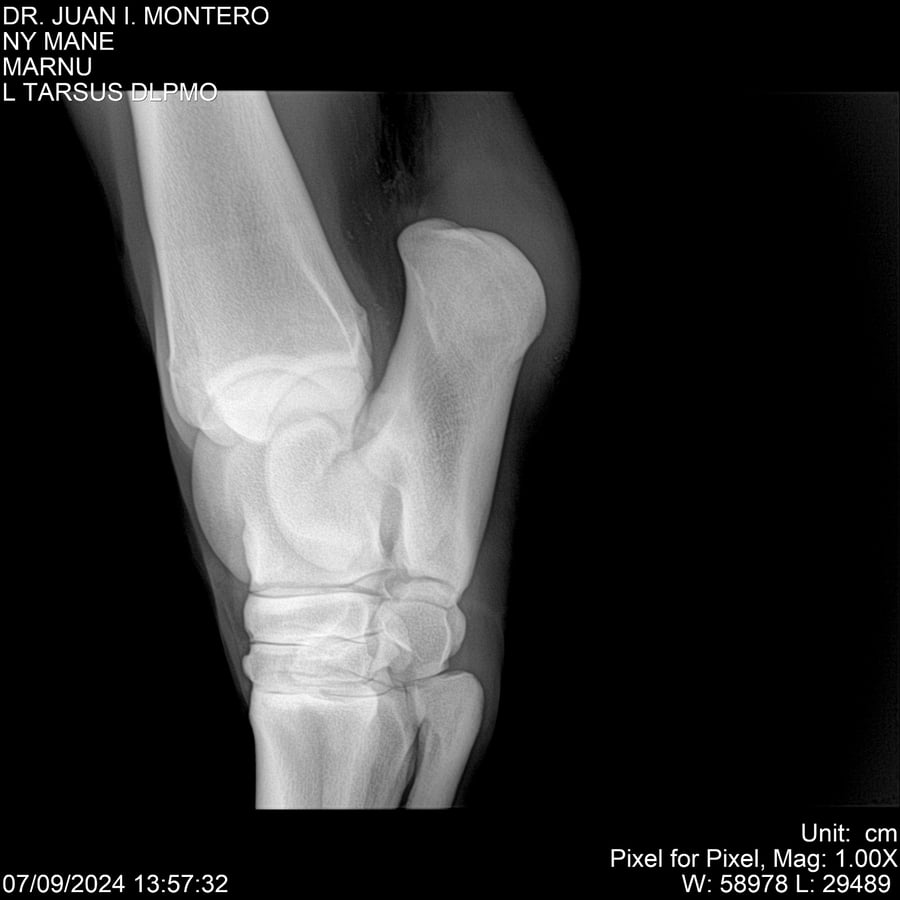

LOTE 20, NY MANE Lote Anterior Volver al remate Lote Siguiente Ficha Contacto Montevideo - Ficha del Lote Identificador: #282520 Categoría: Yeguarizos 76 Visualizaciones ClicData Contacto Empresa: Abelenda N. R., Walter Hugo Nombre*: Teléfono* : E-mail* : Mensaje Enviar Registrese gratis Este contenido Exclusivo está disponible sólo para usuarios registrados Ingresar